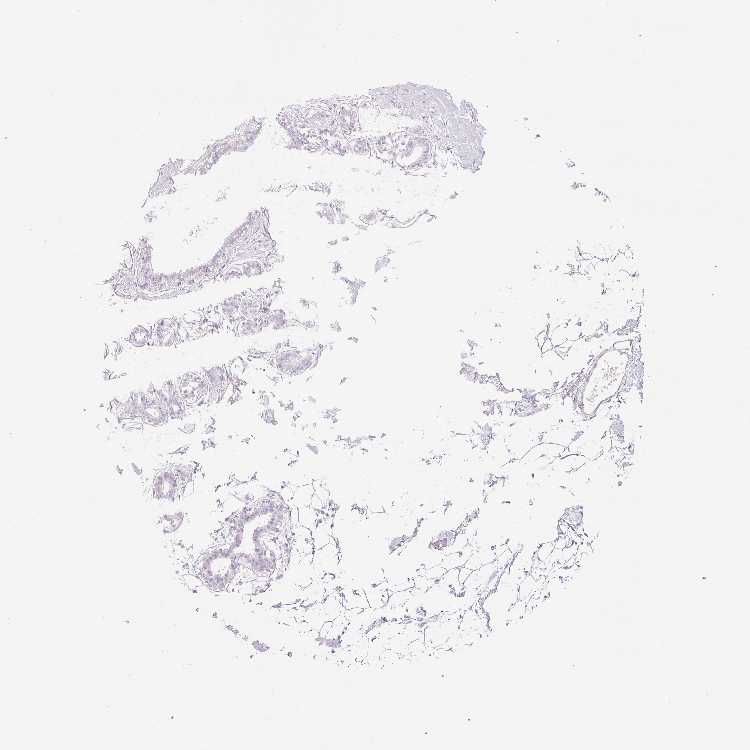

BREAST - Antibody stainingi

Antibody staining in the annotated cell types in the current human tissue is reported as not detected, low, medium, or high, based on conventional immunohistochemistry profiling in selected tissues. This score is based on the combination of the staining intensity and fraction of stained cells.

Each image is clickable and will lead to virtual microscopy that enables deeper exploration of all samples and also displays staining intensity scores, fraction scores and subcellular localization as well as patient and tissue information for each sample.

Antibody HPA043883

Adipocytes Not detected

Glandular cells Not detected

Myoepithelial cells Not detected